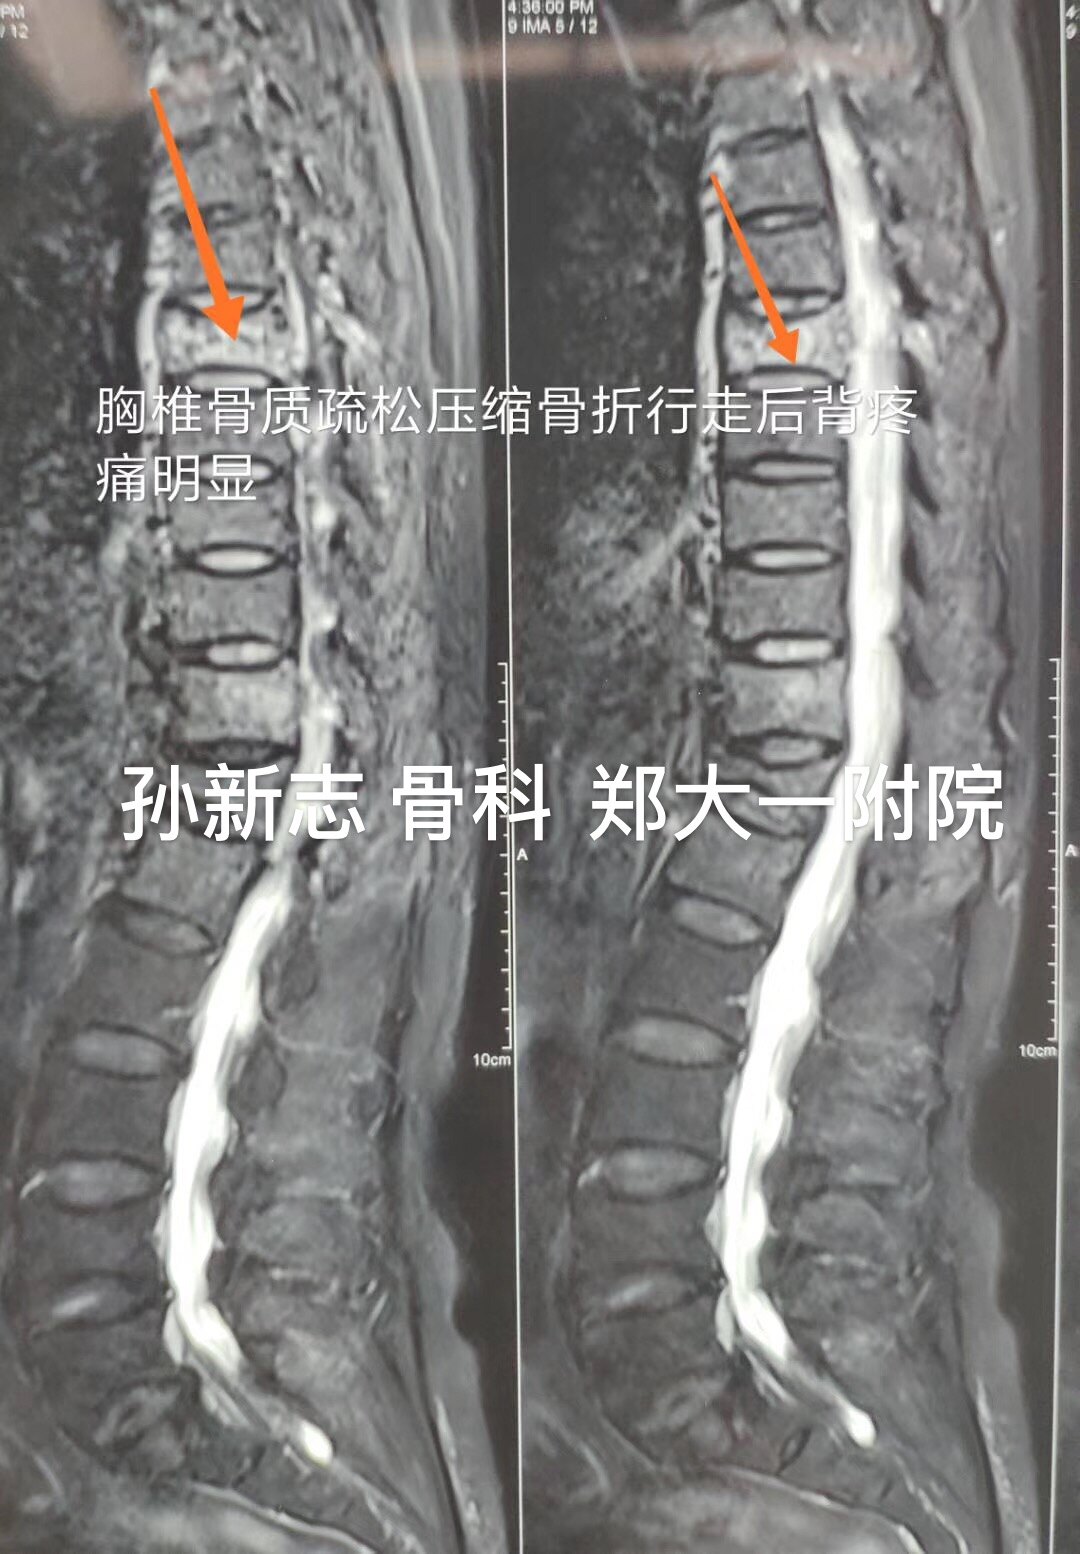

孙新志教授 微创治疗胸椎压缩性骨折病例66